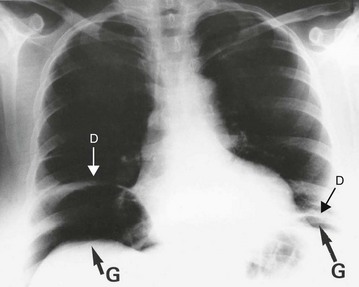

Perforation is essentially a clinical diagnosis but can be confirmed by the presence of free gas in the peritoneal cavity on plain radiography (or CT scan). This is visible as a radiolucent line beneath the hemidiaphragms on an erect chest film (see Fig. 19.8) or a lateral decubitus abdominal film. Note that CT scanning is more sensitive than plain films for detecting small quantities of free gas. Free gas is rare in perforated appendicitis or perforated gall bladder. If imaging fails to support the clinical findings, action should be based on the clinical diagnosis.